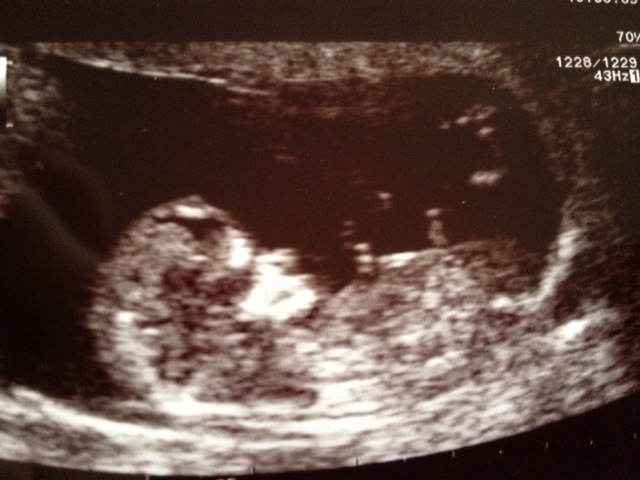

Hi everyone, I'd love to hear what gender you all think my little bundle is. These were taken at 11weeks 5days. Thanks so much in advance for having a look for me :-)

baby looking very younger side can't find the nub clearly

I'm not seeing a clear nub in these images.

Guessing girl from the first pic

Not sure I'm seeing a nub. Skull looks boyish.

maybe boy

Skull is boyish, can't see a nub. Hope for you that it is a boy!